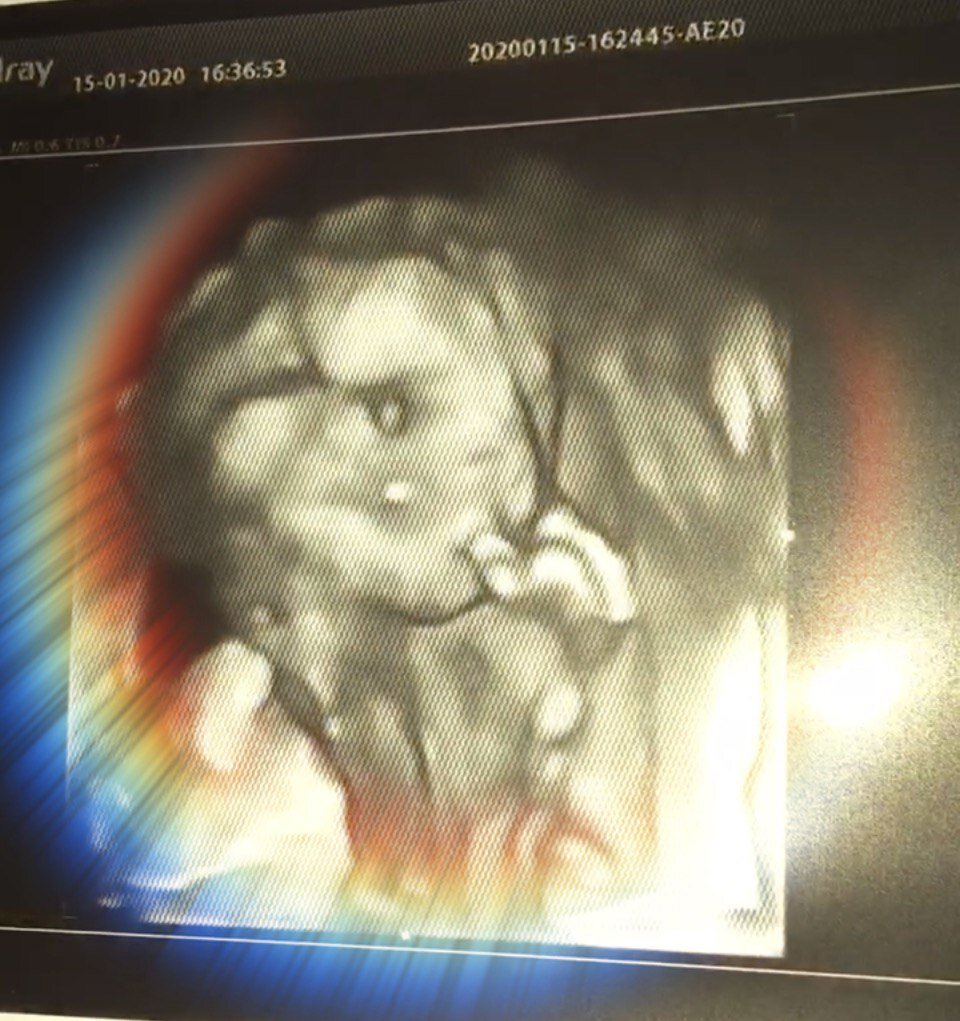

На 19-й неделе у меня прошел скрининг второго триместра. Малыша было четко видно, и он был совсем-совсем похож на человека. Но самое главное в скрининге второго триместра – определение пола ребенка… Девочка! Теперь, узнав, что во мне живет маленькая, замечательная девочка, я вступила в период «гнездования».

Уже видно, что она сосет пальчик.